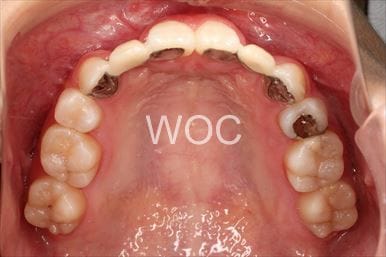

開咬開咬

上下舌側矯正を希望。上顎両側第一小臼歯の抜歯としたが上顎右側第二小臼歯は治療した歯であったため、抜歯部位を変更。治療の難度が上がったため治療期間が少し延長しました。

- 年齢:33歳女性

- 主訴:出っ歯、前歯で噛めない

- 基本矯正料金:1,295,000円

- 治療期間:2年8ヶ月

- 抜歯部位:上顎右側第二小臼歯、左側第一小臼歯

-